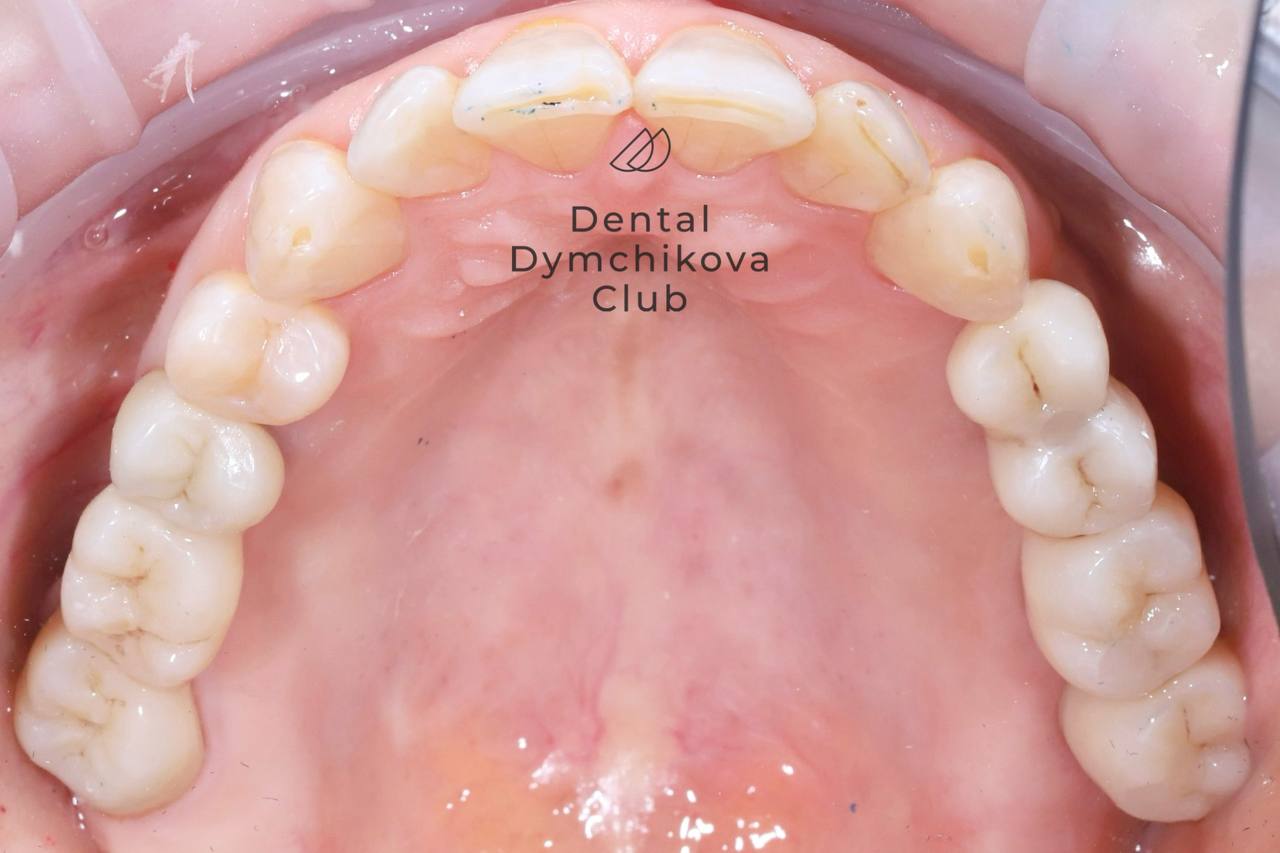

Ортодонтическое лечение, синус-лифтинг, имплантация, протезирование, лечение кариеса

Пациент, 33 года.

Жалобы: на неровные зубы, желание поменять мосты на задних зубах.

Исходные данные: скученность зубов, наличие кариесов, недостаток кости по высоте для установки имплантатов.

Лечение:

1) санация полости рта (лечение кариеса),

2) ортодонтическое лечение (брекеты, минивинты),

3) синус-лифтинг и имплантация в области отсутствующих зубов на этапе ортодонтического лечения,

4) протезирование зубов и имплантатов коронками.

Срок лечения: 2,4 года.

Доктора: Ефимова Дарья Юрьевна, Дымчикова Анна Вавиловна, Лебедева Адиса Тумэновна.